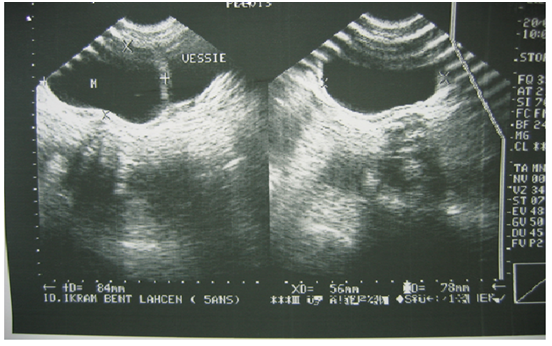

The abdominal ultrasound requested in first intention had mounted a cystic mass, pushing laterally the bladder and could correspond either to a diverticulum of the bladder, or to a cyst of the ovary (Figure 1). CT scan was also performed and had objectified a cystic mass under the umbilical, median compressing behind the bladder dome with overflow to the right of the bladder horn, evoking a cyst of the urachus or an ovarian cyst (Figure 2). Surgical exploration revealed a cystic mass forming part of the bladder dome, evoking a cystic tumor of the urachus. The mass was removed by removing the implantation base from the bladder dome. The postoperative consequences were simple. The pathological report concluded that there was a hydatid cyst of the bladder dome.

Figure 1 Ultrasound image showing a cystic mass pushing back the bladder laterally.